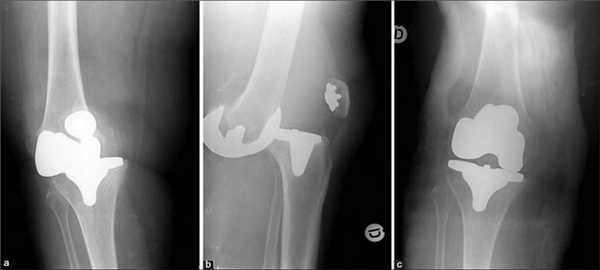

Рентген после операции. Протез стоит корректно.